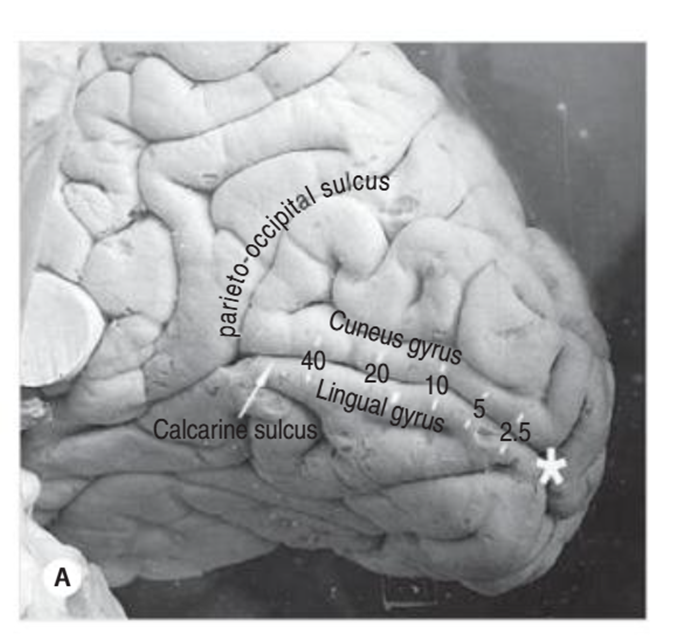

where is the primary visual cortex situated in and what are the 2 main parts of it

The primary visual cortex (V1) is in the occipital lobe

It is split into two main parts:

🔹 Cuneus gyrus → ABOVE the calcarine fissure

🔹 Lingual gyrus → BELOW the calcarine fissure

This division is important because different visual field information goes to each part

the more central vision is - the more posterior in the brain it is processed - fovea will be processed right at the back (star) — and more peripheral part of visual field is dealt with in the anterior part of brain

where do the superior radiations end up in the primary visual cortex

end up in the upper half of the of the visual cortex = Cuneus gyrus - ABOVE calcarine fissure

superior optic radiations carry information from the superior retina - which sees the inferior visual field

where do the inferior radiations end up in the primary visual cortex

end up in the lower half of the visual cortex - lingual gyrus - BELOW the calcarine fissure

inferior optic radiations carry information from the inferior retina - sees the superior visual field

what would damage above the calcarine fissure + below the calcarine fissure result in

Damage above the calcarine fissure (Cuneus) → loss in inferior visual field

Damage below (Lingual gyrus) → loss in superior visual field

explain where the macular fibers end up in the primary visual cortex (3)

More posterior the cortex relates more to central vision

Superior Macular fibers - Cuneus Gyrus - above calcarine fissure

Inferior Macular fibers - Lingual Gyrus - below calcarine fissure